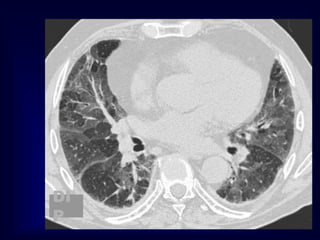

HONEYCOMBING

Defined as - small cystic spaces with

irregularly thickened walls composed of

fibrous tissue.

Predominate in the peripheral and subpleural

lung regions

Subpleural honeycomb cysts typically occur

in several contiguous layers. D/D- paraseptal

Honeycombing is defined by the presence of small cystic

spaces with irregularly thickened walls composed of